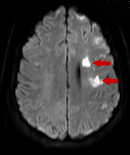

Findings of an MRI scan of the head were significant for multifocal bilateral subacute infarcts, predominantly scattered throughout the left cerebral hemisphere with superimposed multifocal remote infarcts, and vessel occlusion (Figures 1-3).

Figure 1